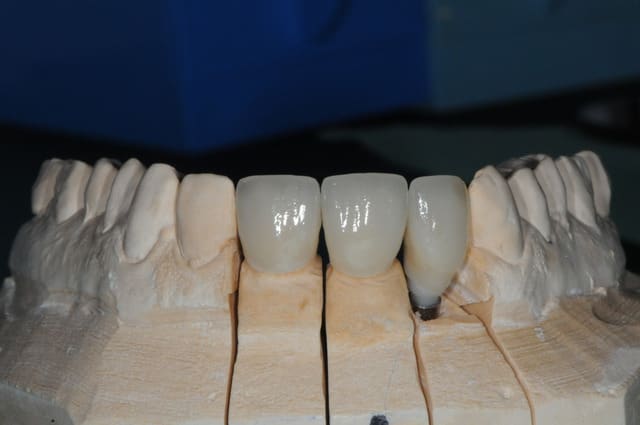

photo :

1- encore quelque temps plus tard

2 mise ne place d'un transfert d'implant pop-in (les nouveaux sont un peu mieux) puis empreinte des dents et de l'implant

3-4-5-6 la réalisation de la prothèse et vue agrandie du pilier en zircone